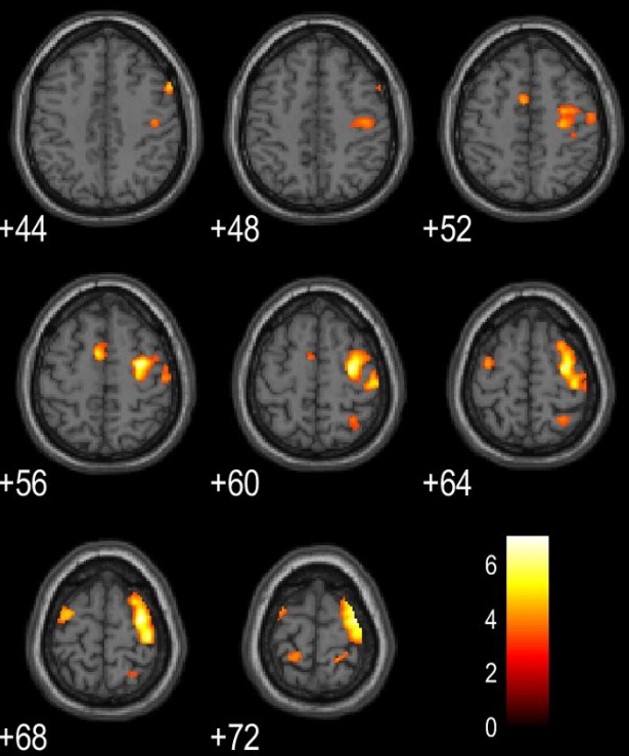

実験によって、さまざまな興味深い成果が得られている。いくつか紹介しよう。〈資料1〉は、利き手でない左手で30秒間運動した後の脳の機能的MRI画像。1回目は脳の活動部位が広範囲にわたるが、回数を重ねるごとに活動部位が減っていることが分かる。スムーズに動かせるようになれば、脳の不要な部位は活動しなくなるわけだ。

<資料1>左手で30秒間運動した後の脳の機能的MRI画像